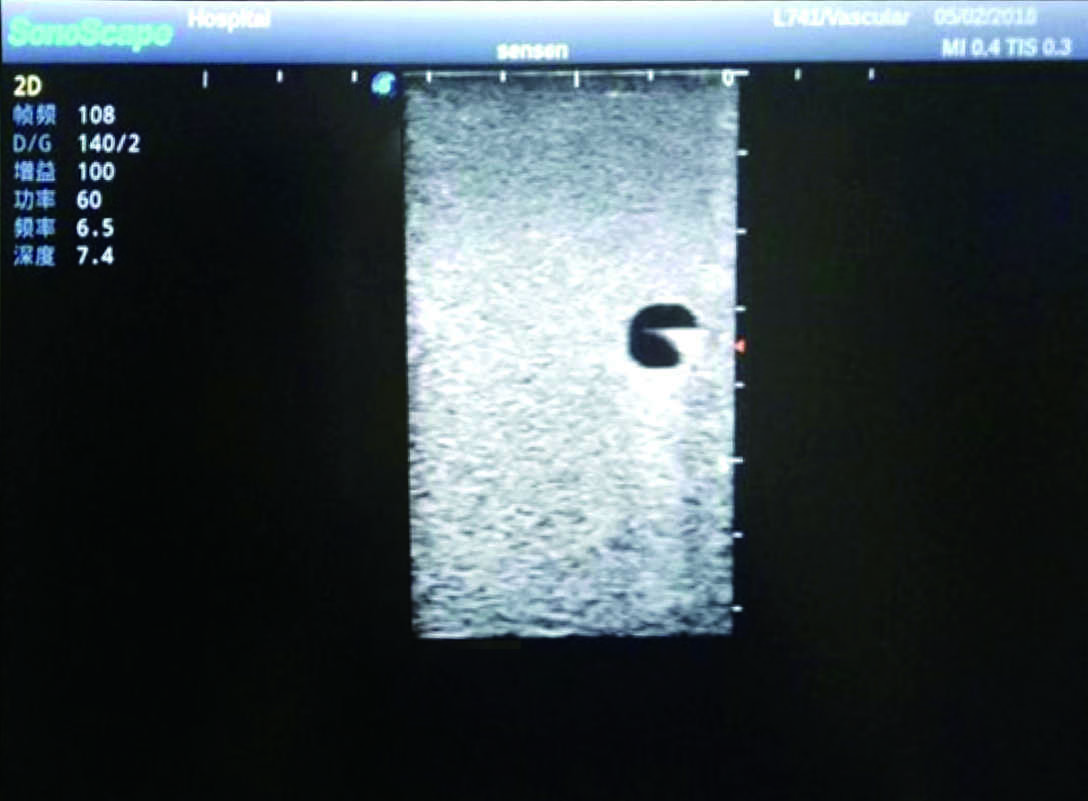

Model TYE1510.1

Outline

It is a model covering up from lobulus auriculae plane to the umbilical plane, and it has anatomical structures like clavicle, rib, sternocleidomastoid, jugular vein and basilic vein.

1)   Made of high molecular polymer ultrasound material, close to the real skin

2)   It can be used by real ultrasound machines

3)   Clear and real images of the tissues and organs (basilic vein and superior vena cava)

4)   When conducting vascular puncture, the piercing can be truly felt, and venous blood outflow can be seen